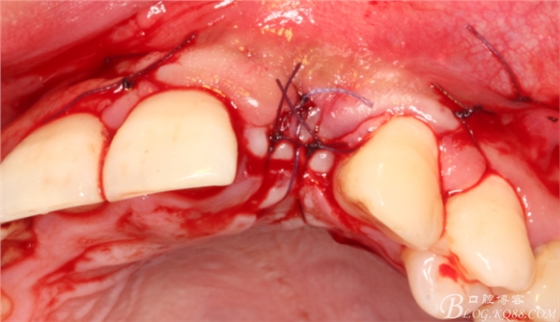

縫合。

4個(gè)月后,唇側(cè)豐滿度尚可,與鄰牙之間齦乳頭完整。